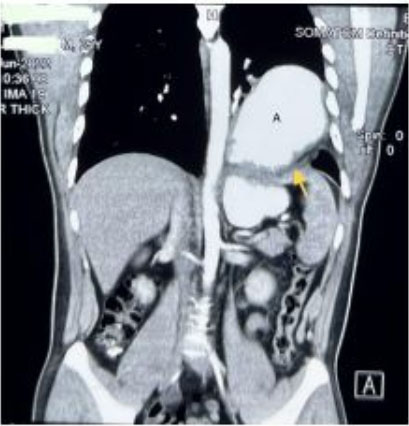

A previously well 9-year-old boy presented with intermittent left upper quadrant pain, anorexia, and weight loss over six months. His past medical history was significant for being born preterm at 34 weeks’ gestation and requiring ventilatory support as a neonate. Computed tomography (CT) scan (Figure 1 and Figure 2) showed a 10 cm encapsulated spherical mass appearing to arise from the pancreatic tail. The working diagnosis was a cystic pancreatic tumour, and he was referred for further management.

Figure 1: CT coronal view 114 mm × 97 mm retroperitoneal cystic mass displacing the left colon, pancreas, and small bowel.